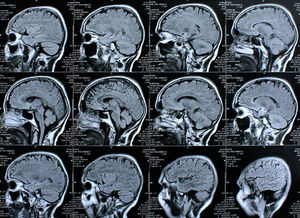

Gehirne: Bewegung verbessert Struktur erheblich (Foto: pixelio.de, Rike) |

MRI-Scans durchgeführt

Das Team um Cyrus A. Raji analysierte die Daten von 876 Teilnehmern der 30 Jahre laufenden Cardiovascular Health Study. Zu langfristigen Untersuchung des Gedächtnisses gehörten auch Standardfragebögen zu den Gewohnheiten körperlicher Aktivitäten. Bei den durchschnittlich 78 Jahre alten Teilnehmern wurden auch MRI-Scans des Gehirns durchgeführt.

Mit Computer-Algorithmen wurde das Volumen von Gehirnstrukturen analysiert, die beim Gedächtnis oder wie der Hippokampus bei Alzheimer eine Rolle spielen. Die körperlichen Aktivitäten der Personen wurden mit dem Gehirnvolumen in Beziehung gesetzt. Zu diesen Aktivitäten gehörte eine Vielzahl von Interessen von Gartenarbeit bis zum Trainieren in einem Fitness-Studio. Auch die Folgen auf den wöchentlichen Kalorienverbrauch wurden untersucht.